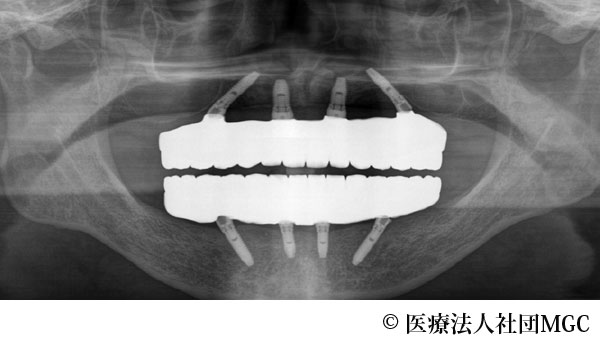

【症例3】上下All-on-4(オールオンフォー)

- 治療後

- 治療名

- 上下All-on-4(オールオンフォー)

- 費用

- 5,888,300円(税込)

- 期間

- 6ヵ月

治療内容

患者様の症状

上のブリッジが取れたことをきっかけに、全体に歯をきれいにしたいとご来院されました。

治療法

ご相談の結果、患者様の生活の質(QOL)を向上させ、しっかり噛め、審美的にも重視した、上下All-on-4(オールオンフォー)を行いました。

治療結果

機能性、審美性ともに改善し、満足していただけました。

※治療結果は患者様によって個人差があります。

治療を行う上での注意点(リスク・副作用)

インプラント周囲炎の可能性、まれに歯が欠ける可能性があります。